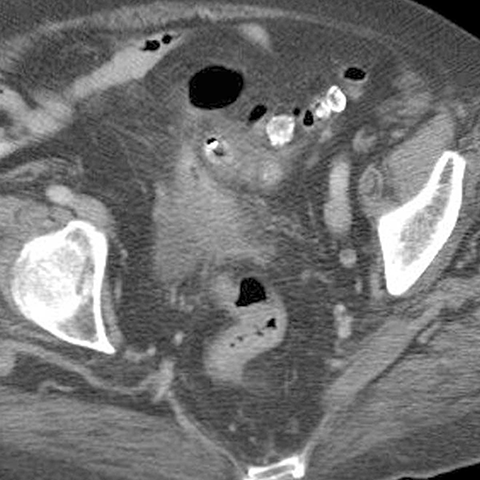

65 year-old male presents with fever and LLQ pain. [4 of 5]